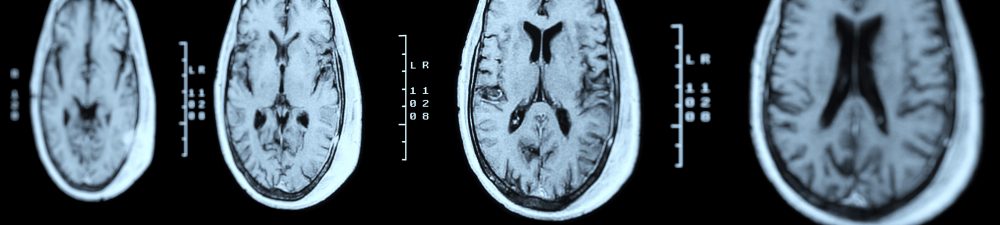

Welcome to the University of Edinburgh’s Centre for Dementia Prevention, which combines research in science, medicine and social sciences to lead global efforts in preventing dementia.At our heart is a vision to bring together researchers, policy makers and members of the public, to achieve three goals: